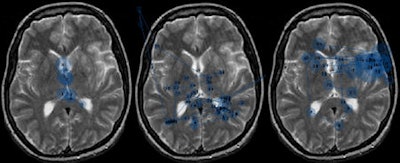

However, Toms added that to an extent, all radiologists -- senior or not -- instantly recognize certain information. He invited the audience to read a brain CT image for 200 msec that he flashed on the screen. Everyone easily recognized the abnormalities. "This is recognition using subconscious thought processing: system one," he explained.